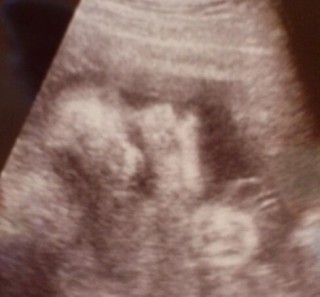

2Dエコー写真ですが、ここまではっきり見えたのは始めてでしたがはじめは何の写真か解らず、もしかして顔?と。。。次回の妊婦検診のときに、確認しました☆ 鼻の骨大きめ?ますます、早く会たくなっちゃいますね♪ ベビちゃん。たぶん女の子だろうと。